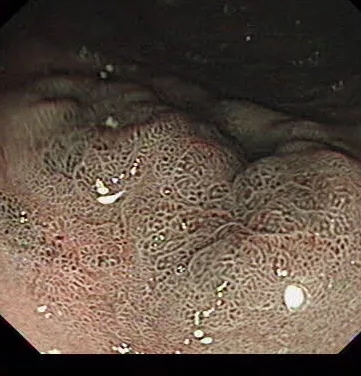

其后,陈先生来到了郑州大学五附院,消化内科一病区大夫了解基本病情过后,安排陈先生住院做个放大加染色胃镜再复查一下。而在放大加染色胃镜下,消化内科一病区的胡威大夫发现了一些不同寻常的问题:病人胃窦部的粘膜有明显的腺管结构和血管形态异常。胡大夫认为这是一个早期的癌症!紧接着就在放大胃镜指导下在考虑癌变位置精准取了病理活检送去化验。

三天过后病理结果出来了:“胃窦粘膜高级别上皮内瘤变,胃幽门处粘膜低级别上皮内瘤变”。一处早癌、一处癌前病变。得到这个消息后陈先生的家属陷入了不解和焦虑之中,上个月做的胃镜结果还在手里,怎么没过多久就得了癌呢?